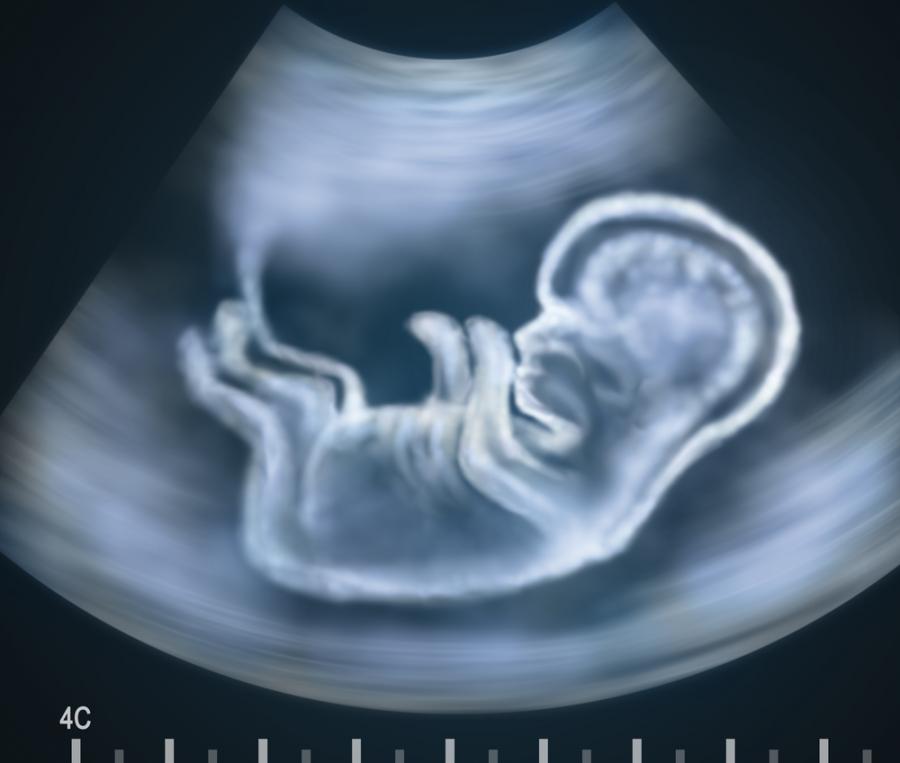

Днес ултразвуковият апарат не учудва никого, всички жени, които искат, научават пола на бебето си далеч преди да родят, дори вътреутробните операции на плода вече не са екзотика.

Благодарение на ултразвуковата техника

нещата се променят. С нея лекарите успяват да надникнат и да следят какво се случва в утробата на бъдещата майка и как се развива нероденото човече вътре. И правят удивителни открития!